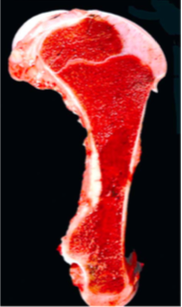

Describe this lesion in a horse!

Hemangiosarcoma invading the bone and bone marrow